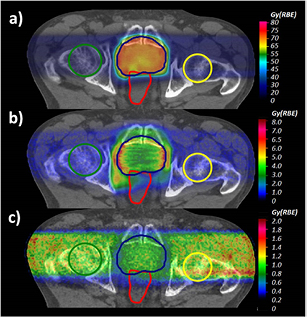

Standard image High-resolution imageFigure 7 (upper panel) depicts MC-calculated  distributions applying the biological model introduced in this work and in Mairani et al (2016b) for both Z = 1 and Z = 2 particles for the prostate treatment plan.

distributions applying the biological model introduced in this work and in Mairani et al (2016b) for both Z = 1 and Z = 2 particles for the prostate treatment plan.  differences between full calculations, as in panel (a), and the current clinical approach, i.e. applying a constant RBE of 1.1, are shown in panel (b). Similarly to McNamara et al (2015), the largest differences, up to about 7 Gy (RBE), have been found in the distal part of the two opposing fields due to the higher LET component (Grassberger and Paganetti 2011). In these regions RBE values of about 1.3 have been found, while the mean RBE in the PTV is about 1.18, i.e. about 7% higher than the clinical applied value of 1.1. In terms of physical dose, for dose values larger than 1% of the planned dose, the contribution of Z = 2 and Z > 2 particles was about 1.2% and 0.6% in the EC and about 0.6% and 0.3% in the PTV.

differences between full calculations, as in panel (a), and the current clinical approach, i.e. applying a constant RBE of 1.1, are shown in panel (b). Similarly to McNamara et al (2015), the largest differences, up to about 7 Gy (RBE), have been found in the distal part of the two opposing fields due to the higher LET component (Grassberger and Paganetti 2011). In these regions RBE values of about 1.3 have been found, while the mean RBE in the PTV is about 1.18, i.e. about 7% higher than the clinical applied value of 1.1. In terms of physical dose, for dose values larger than 1% of the planned dose, the contribution of Z = 2 and Z > 2 particles was about 1.2% and 0.6% in the EC and about 0.6% and 0.3% in the PTV.

Figure 7. a) MC-calculated  distribution applying the introduced RBE models for both Z = 1 and Z = 2 particles for the prostate case. (b) Differences between MC-calculated

distribution applying the introduced RBE models for both Z = 1 and Z = 2 particles for the prostate case. (b) Differences between MC-calculated  displayed in (a) and that obtained using the clinical constant RBE of 1.1. (c) Differences between MC-calculated

displayed in (a) and that obtained using the clinical constant RBE of 1.1. (c) Differences between MC-calculated  displayed in (a) and applying the introduced RBE model weighting only the Z = 1 particles. The PTV, the femurs and the rectum are displayed with lines.

displayed in (a) and applying the introduced RBE model weighting only the Z = 1 particles. The PTV, the femurs and the rectum are displayed with lines.

Download figure:

Standard image High-resolution imagePanel (c) of figure 7 shows the differences between  values obtained with the full calculations and taking into account the biological effect of only the Z = 1 particles using equation (1) and the LET-dependent part of equation (2). Weighting the biological effect of He secondaries increases the mean

values obtained with the full calculations and taking into account the biological effect of only the Z = 1 particles using equation (1) and the LET-dependent part of equation (2). Weighting the biological effect of He secondaries increases the mean  by about 0.9 Gy (RBE) in the PTV and by about 1.13 Gy (RBE) for the femurs in the EC. The latter means about 5% higher

by about 0.9 Gy (RBE) in the PTV and by about 1.13 Gy (RBE) for the femurs in the EC. The latter means about 5% higher  .

.